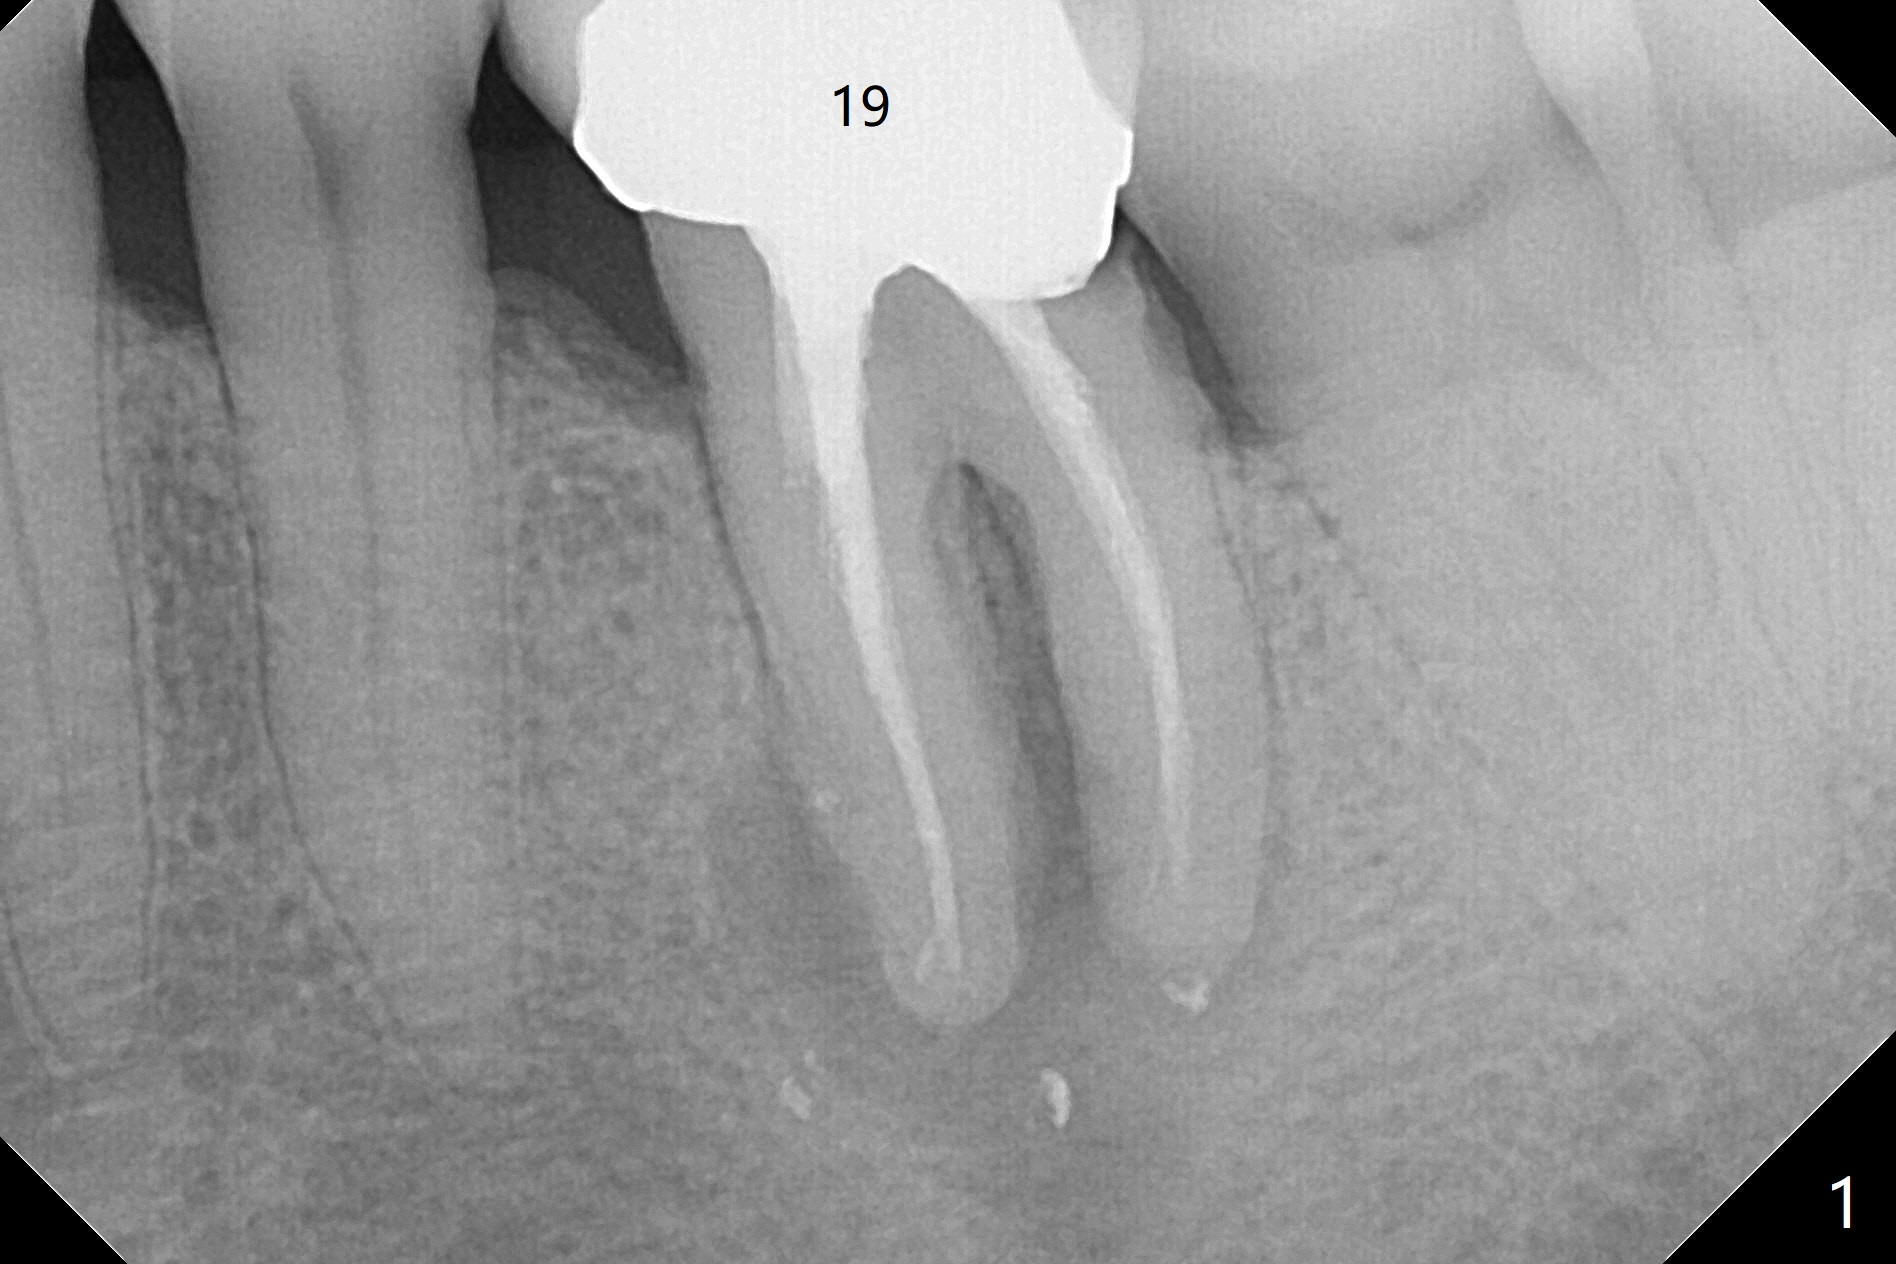

Extraction of the tooth #19 with large PARL (Fig.1,2) confirms the loss of buccal plate, but the crestal bone exists. After failure to place an implant in the middle socket with removal of the lingual septal bone, socket preservation is done with PRF and sticky bone (Fig.3). There is possibility to place a ~4 mm implant in the mesial socket (Fig.4). Or just drop a 5x11 mm Bicon Implant into the large socket, surrounded by sticky bone. When periodontal dressing is removed 18 days postop, the bone graft seems to remain to be "sticky" yellowish, while the granulation tissue has started to grow into the center of the socket from the previously buccal and lingual furcae (Fig.5 reddish). Granulation tissue seems to cover the bone graft (Fig.6), although there is smells when the periodontal dressing is removed. Bone height reduces nearly 3 months postop (Fig.7). The buccal plate collapses (Fig.8), but there seems no further bone loss 4 months postop (Fig.9). Because of buccal plate loss, an implant will be placed lingually with guide (Fig.10-12 green). Bone graft may be placed buccally after implant placement with probing.